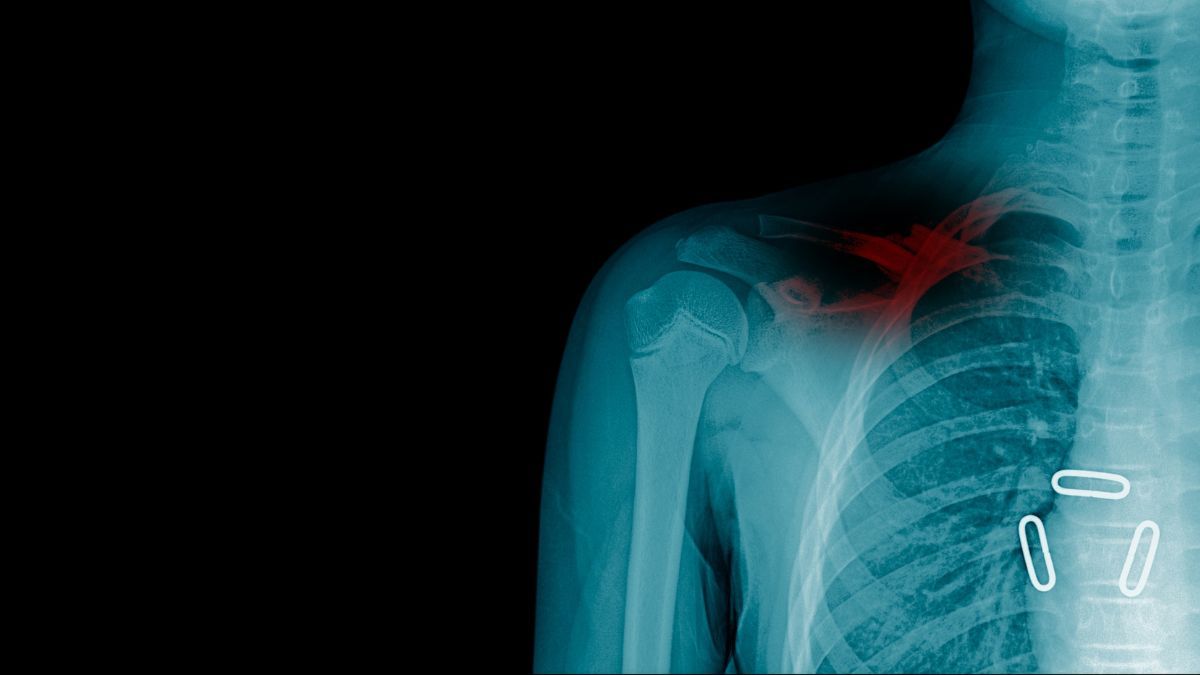

1. Patah Tulang Selangka

Patah tulang selangka adalah kondisi ketika klavikula kamu mengalami retak, patah, ataupun pecah. Kondisi ini umumnya disebabkan oleh cedera akibat olahraga, kecelakaan, ataupun terjatuh dengan lengan yang terulur.

Disampaikan dr. Arina Heidyana, ketika tulang selangka patah, maka lengan kamu akan susah digerakkan.